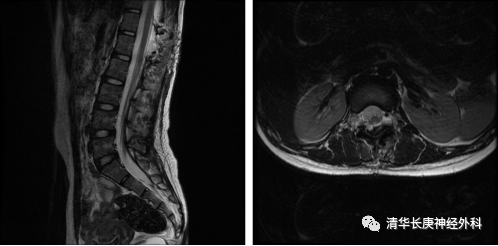

术后磁共振示囊肿基本消失,神经受压缓解

患者安返病房,术后2天复查核磁提示囊肿基本消失,无明显的神经功能障碍,实现了微创与精准手术治疗设想。看到小姑娘和父母高兴地出院,王贵怀欣慰地说道,“医师要敢于探索,善于思考,利用灵活适宜的技术和理念服务患者。”